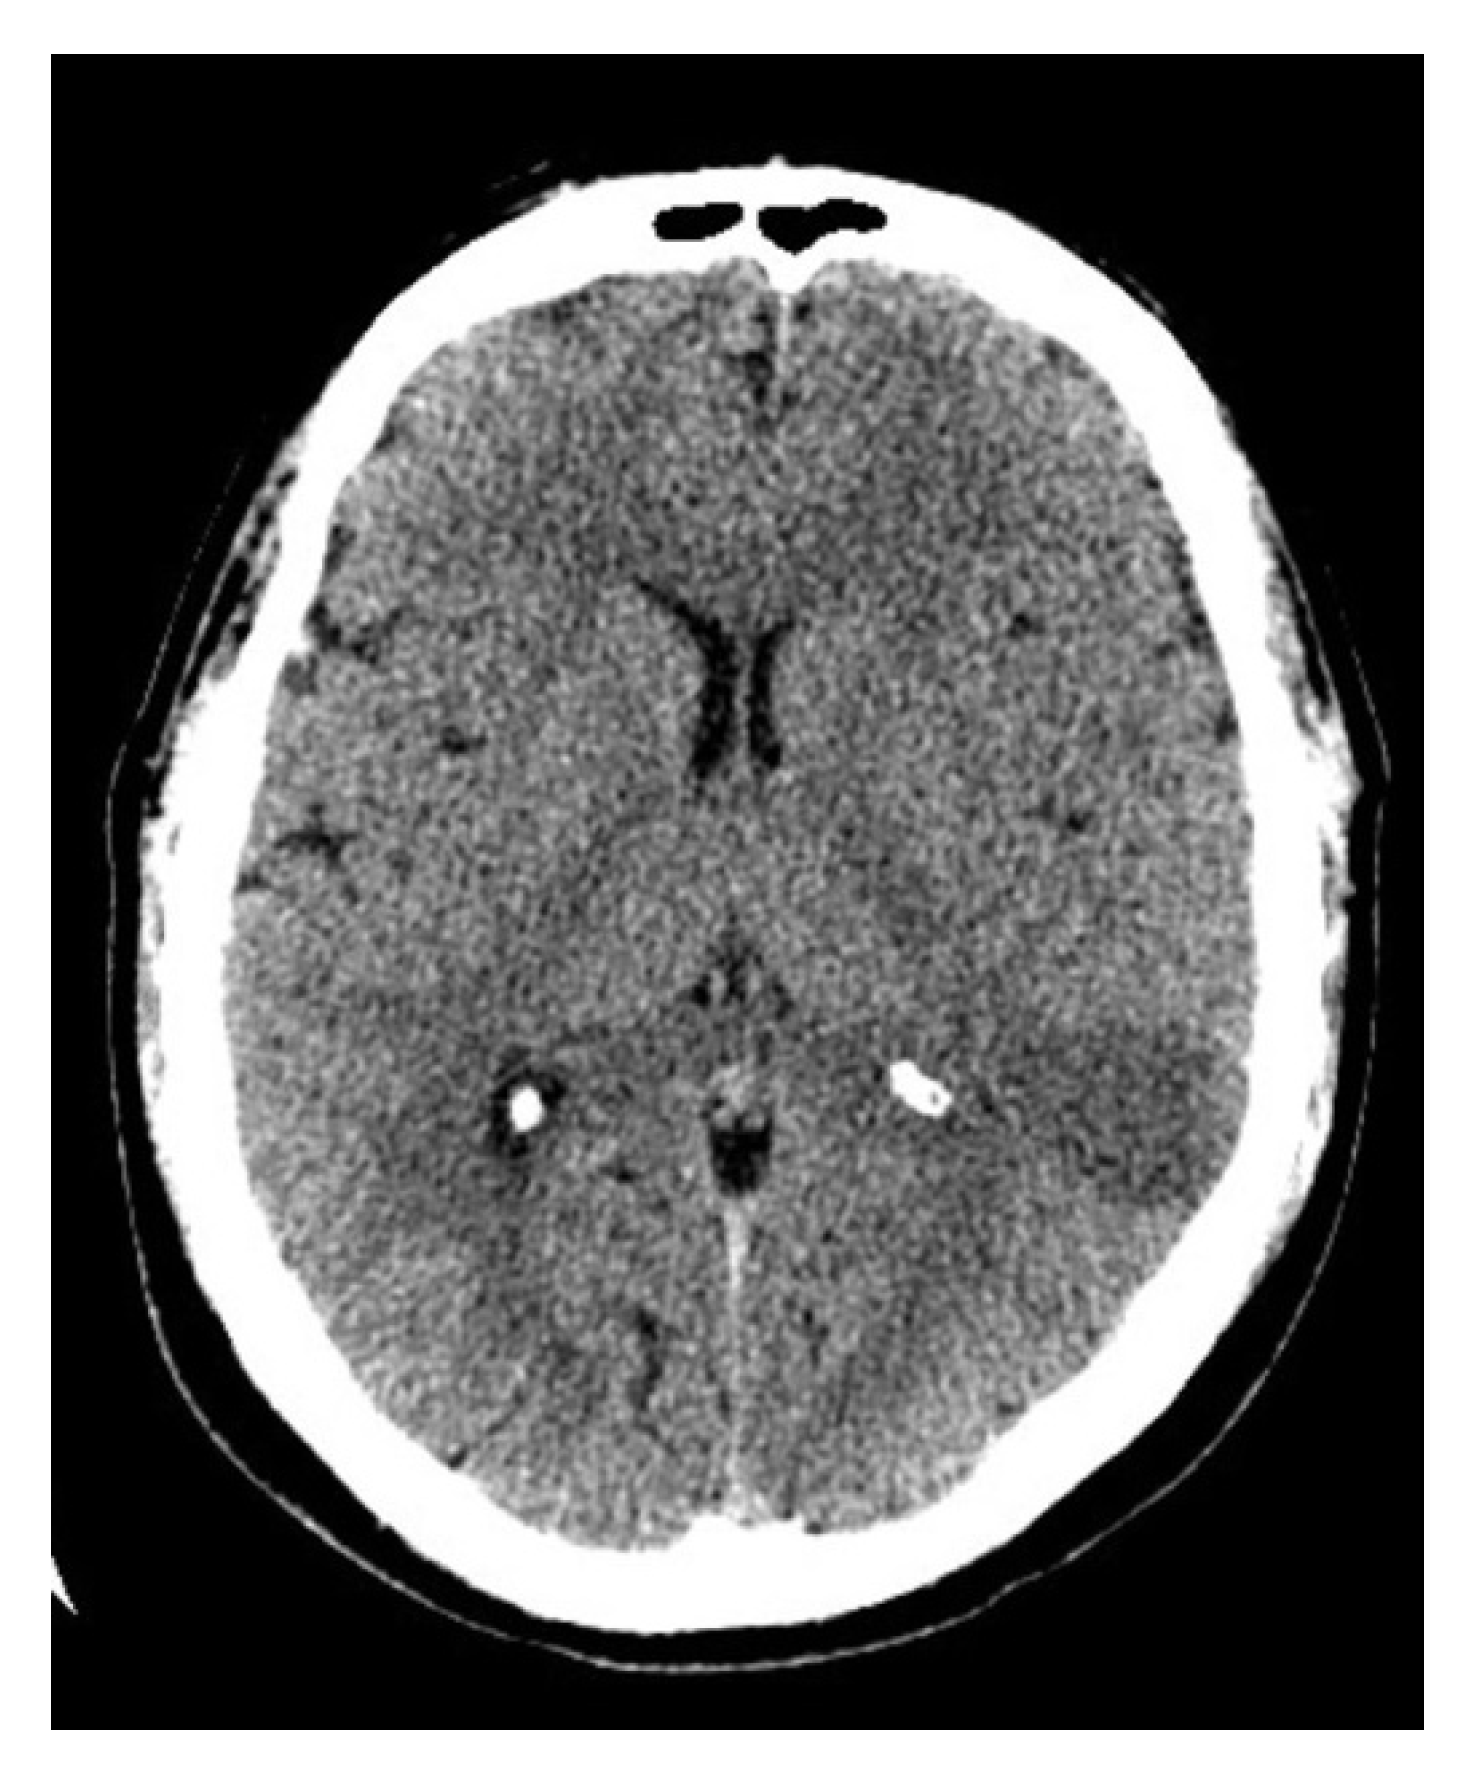

2. Case

2.1. Case History